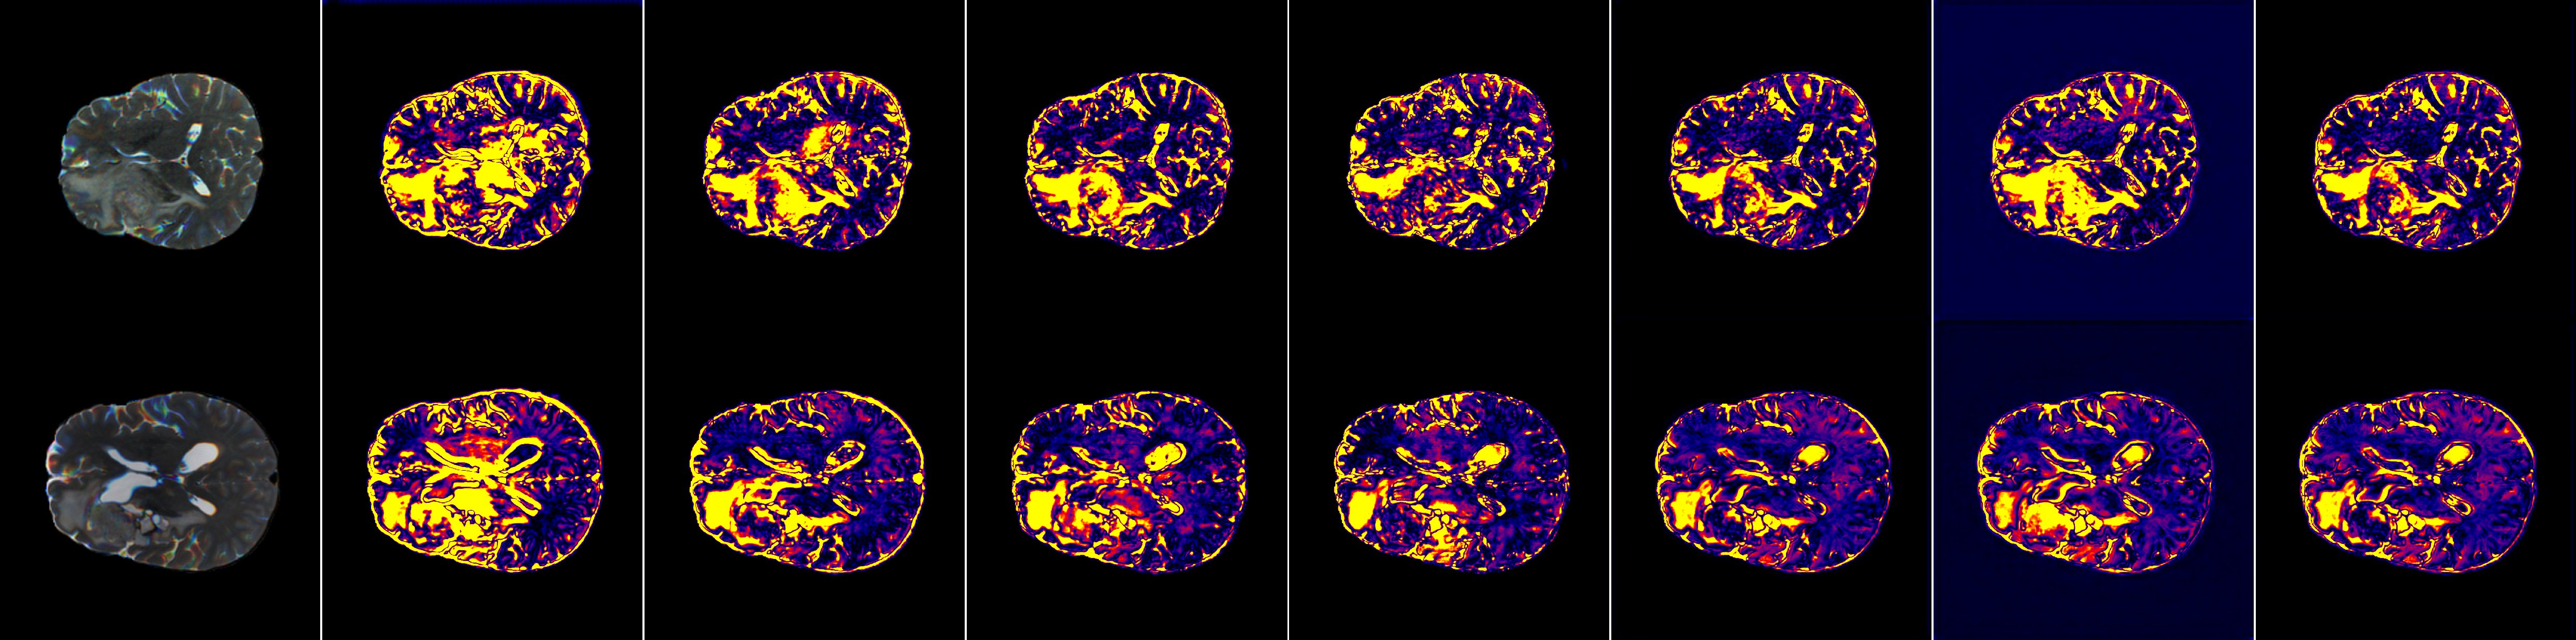

Refer to caption

Figure 6: Comparison of error heatmaps (Part 1/2), provided as a supplementary visualization to the main experimental error analysis.